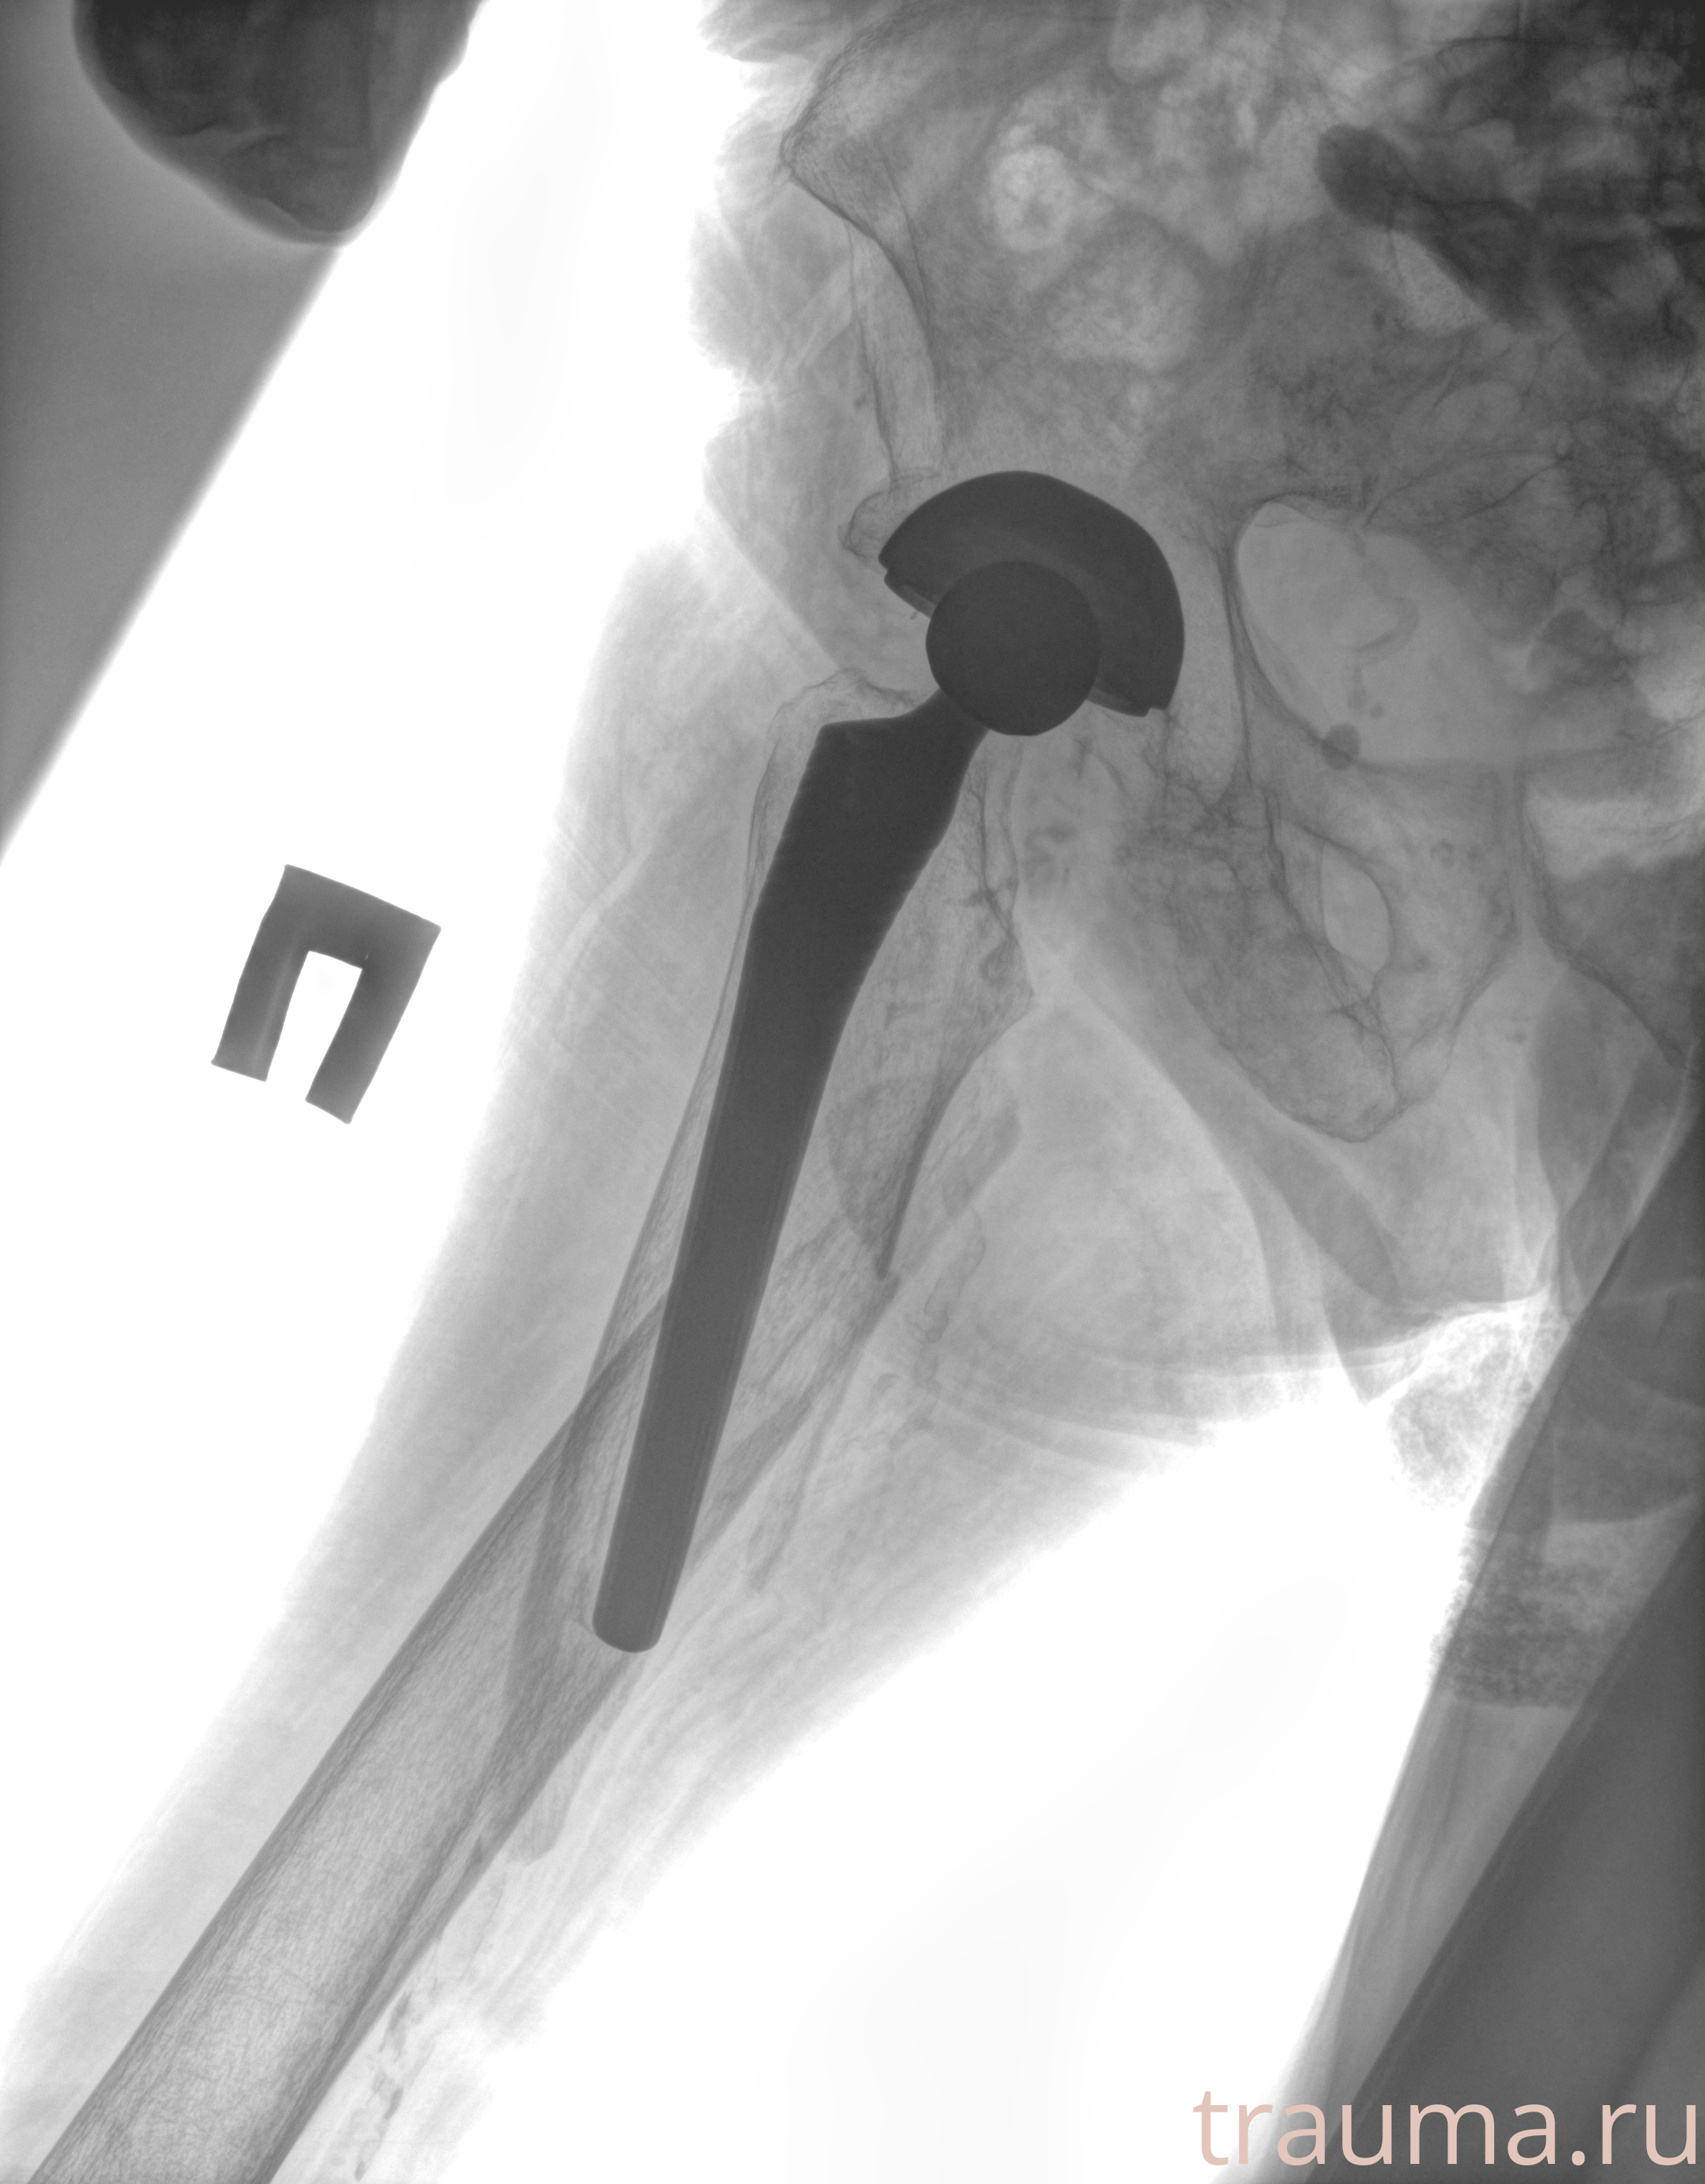

Рентгенограммы

Рентген на дому: по вашему адресу приезжает врач-рентгенолог, травматолог-ортопед с мобильным рентгеновским аппаратом, проводит диагностику травмы или заболевания, делает необходимые рентгенограммы, дает рекомендации по дальнейшему лечению. Получить качественные снимки в домашних условиях возможно благодаря уникальной методике, разработанной МосРентген Центром для института  Склифосовского